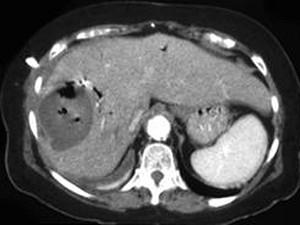

问题 男,48岁,寒战高热,右上腹痛一天,CT检查如图所示,最可能的诊断是 ( )

选项 A、肝错构瘤 B、肝转移瘤 C、肝脓肿 D、胆管细胞癌 E、原发性肝癌

答案 C